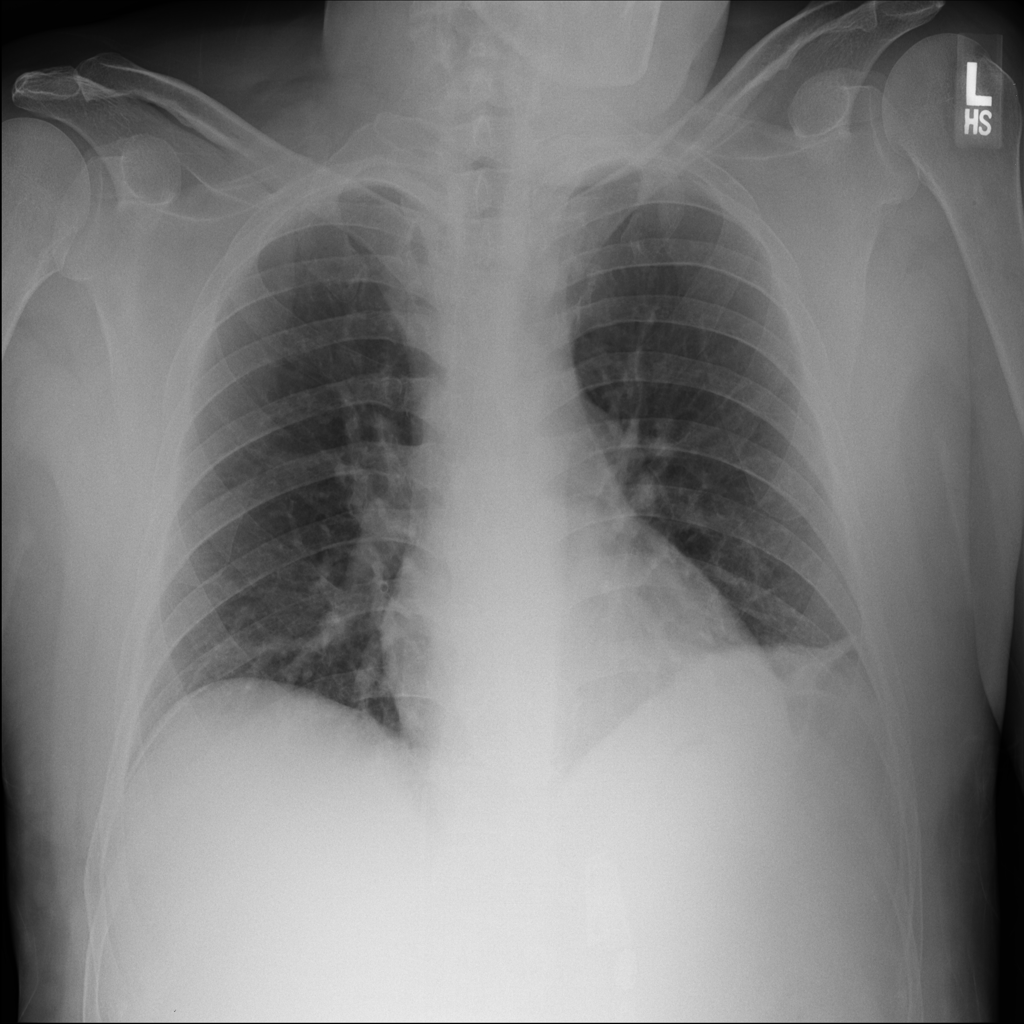

PAT-DB80 · IMG-000Atelectasis

PAT-DB80 · IMG-000

PA